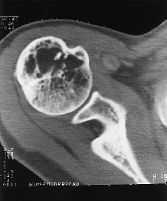

Las radiografíasrealizadas en vértebra L-IV (fig. 2A) y en la TAC (fig. 2B)confirman estas imágenes, apareciendo sobre las lesioneslíticas una imagen de vidrio en polvo, característicade displasia fibrosa.

Figura2B.